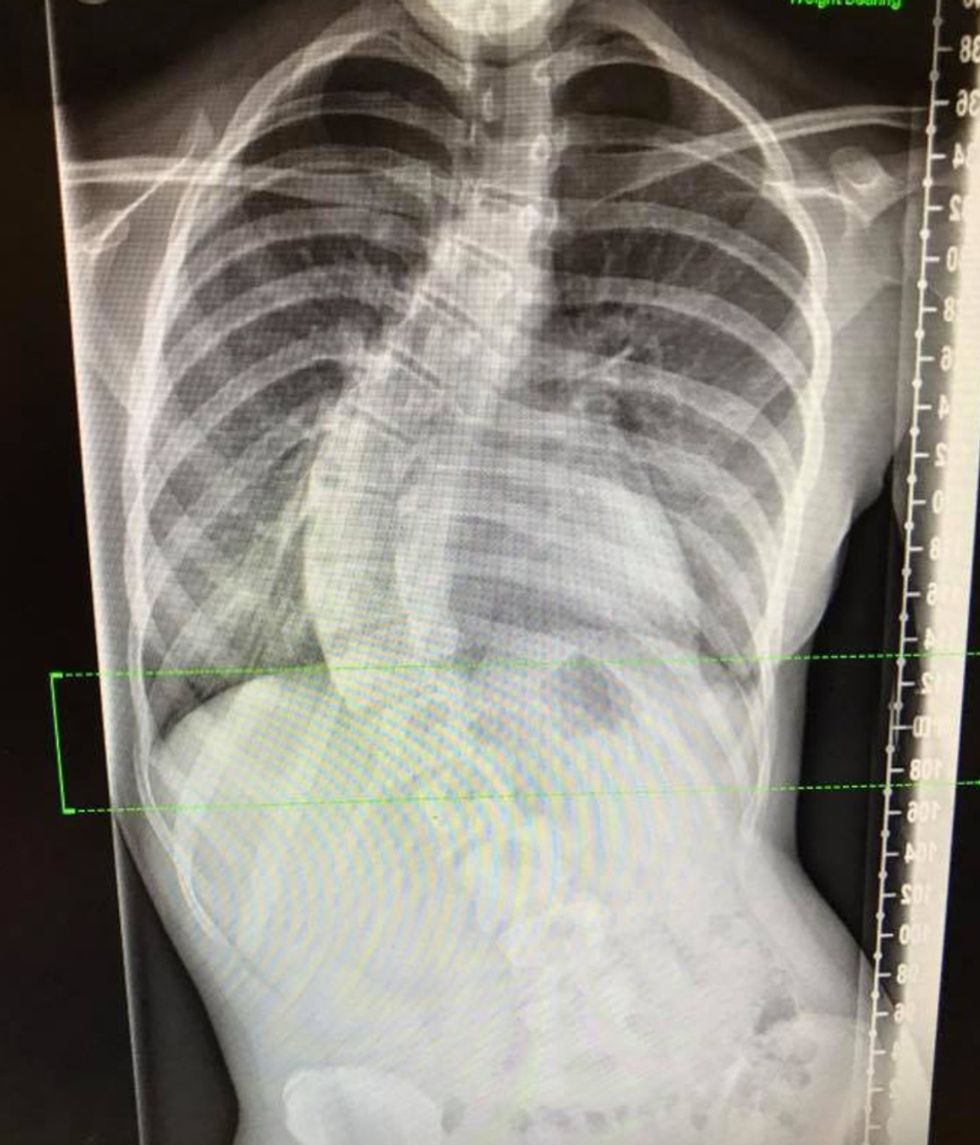

“But by the time I saw it on holiday in Greece a year later, her spine was straight at the bottom, then curved at the top, like a question mark."

Julie took her to the doctor, who diagnosed scoliosis—a condition where the spine twists and curves to the side.

Referred to a specialist at Leeds General Infirmary in September 2016, she was told Lily would eventually need surgery in the future, or it could lead to an irreversible deformity.

“Initially, she didn't want such a major operation. But the curve had got worse and before the operation was curved at 70 degrees."